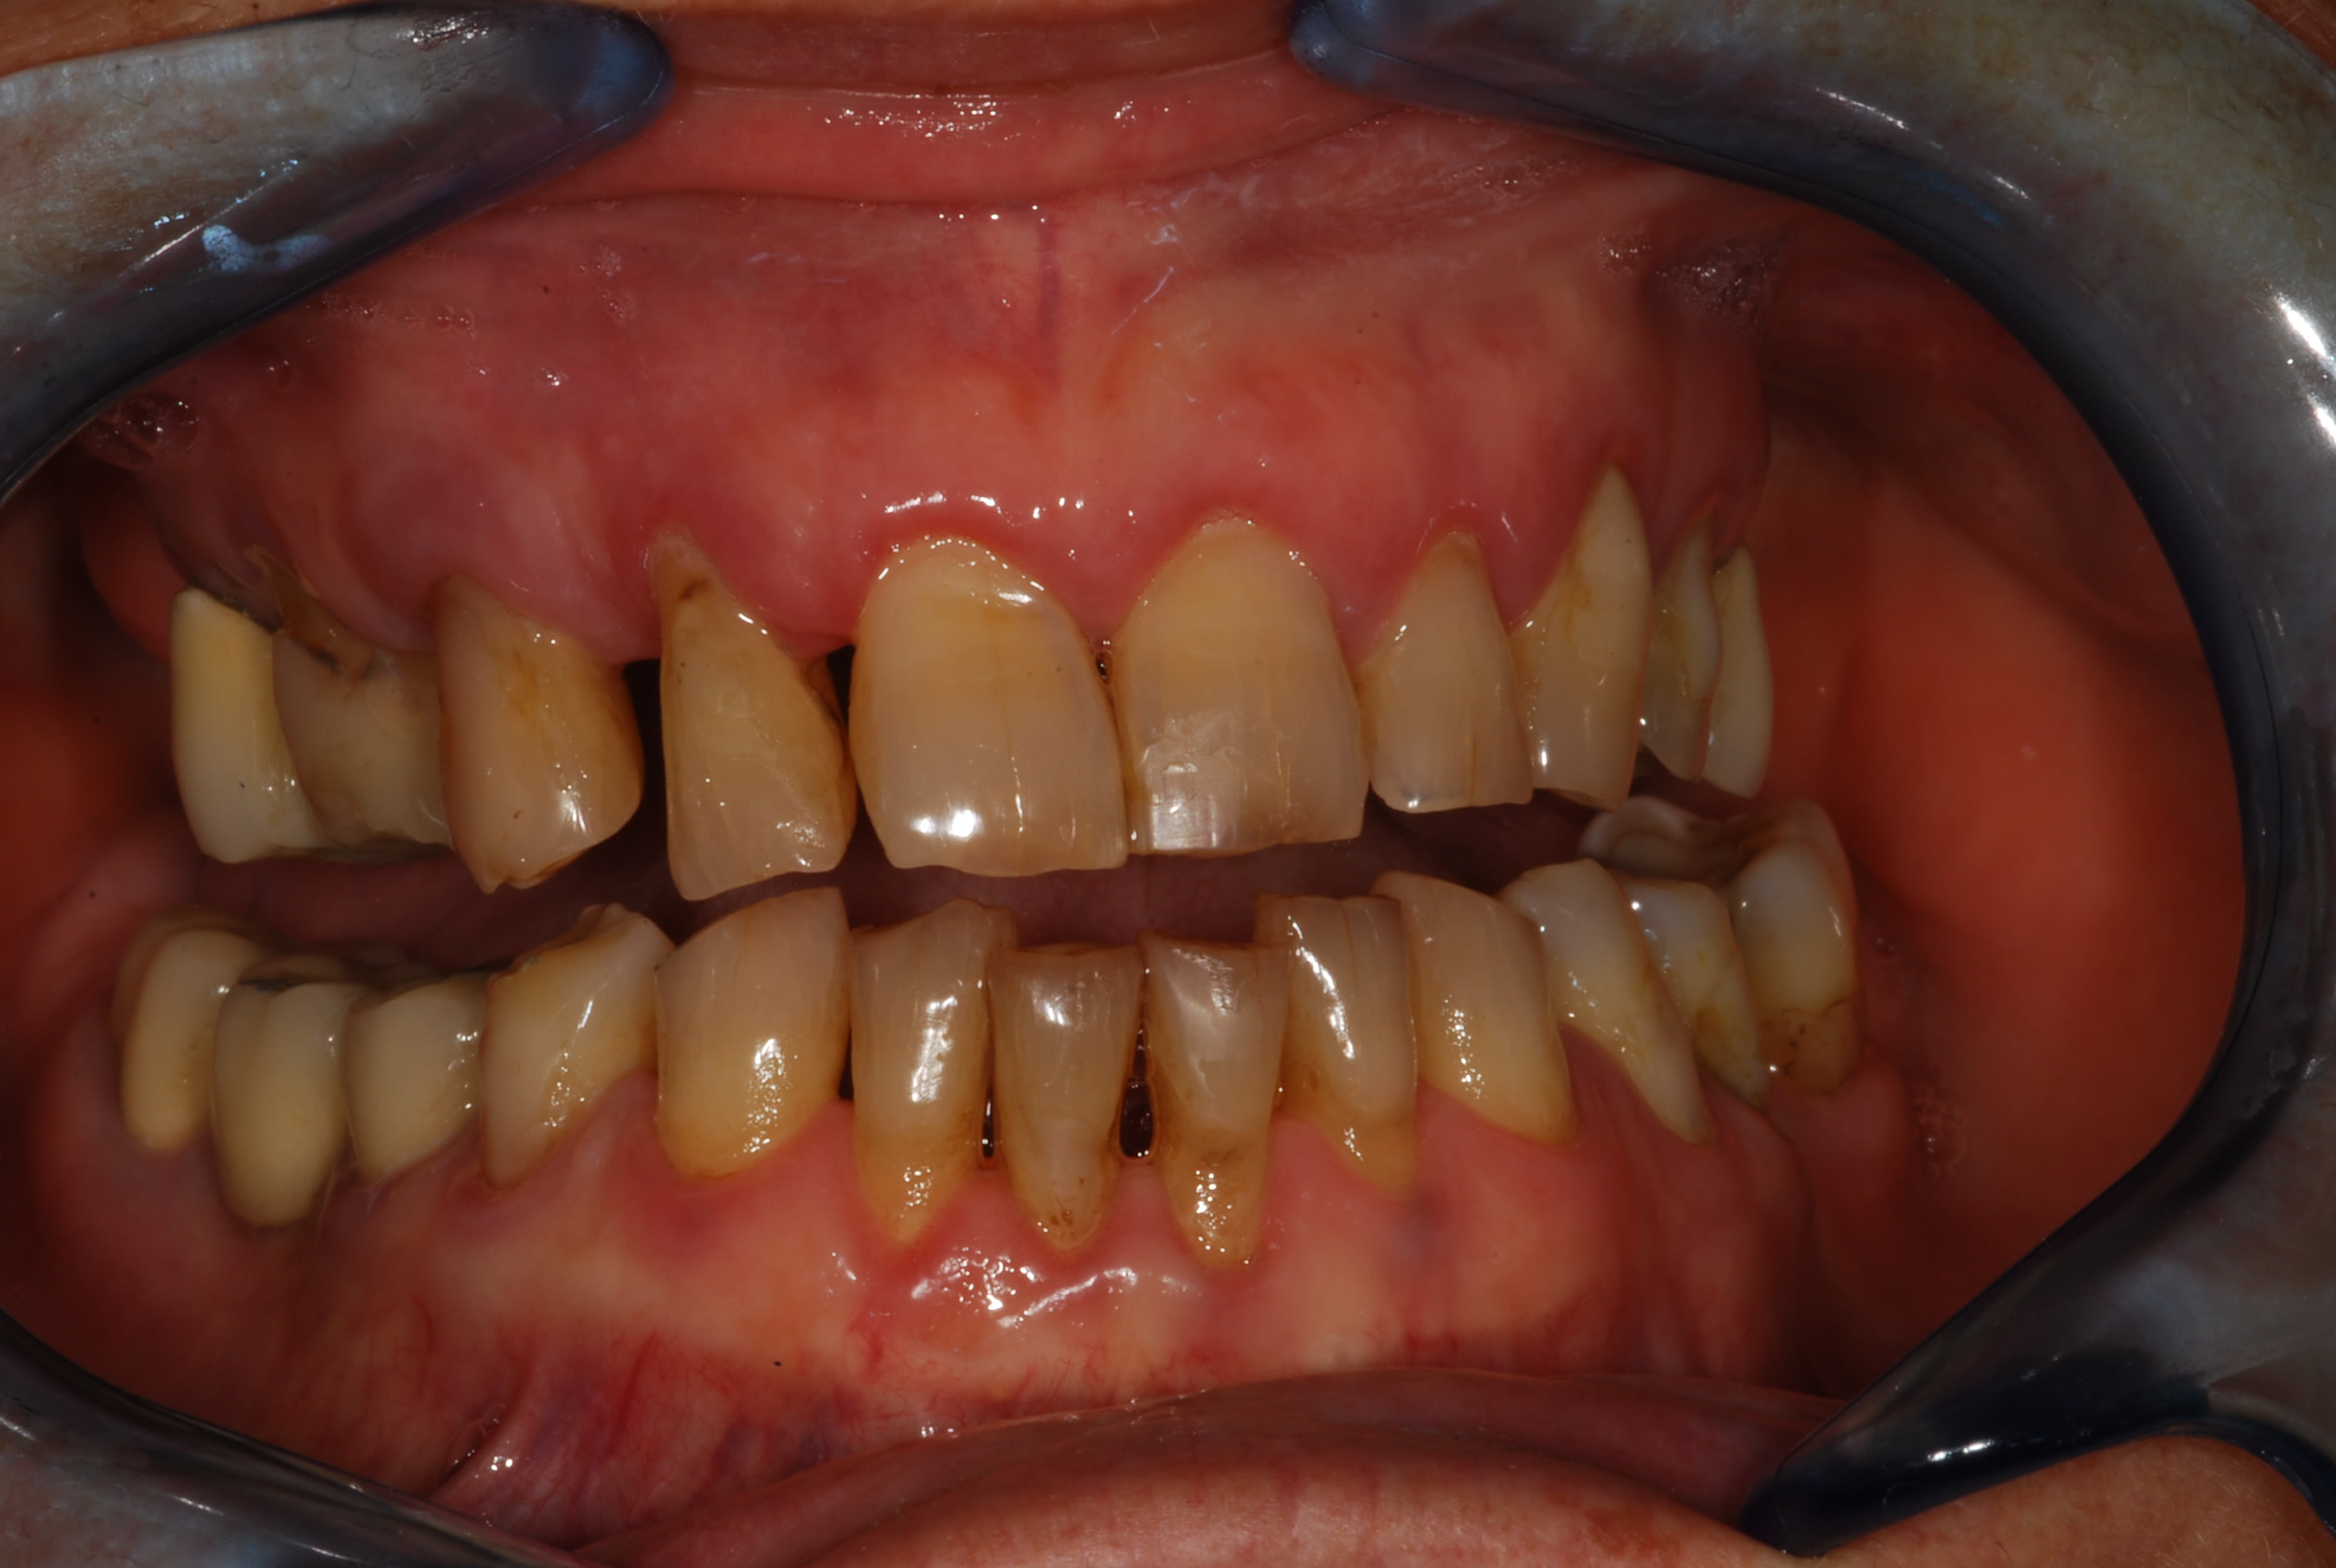

Bonjour à tous,

Voici comme prévu les photo du cas, j'ai pris les empreintes ce jour donc je posterais des photos des moulages dès que le proto les aura coulés !

Esthétique... Combler les diastèmes, teinte etc. et accessoirement pérenniser ses dents...

je suppose que le pt inter incisif n est pas au milieu de la figure , je me trompe ?

on dirait que le secteur 20 est parti à gauche , y compris la 11 , et qu a partir de la 11 le secteur 10 s est vestibulé . donc je confirme que tu ne peux faire le haut sans le bas .